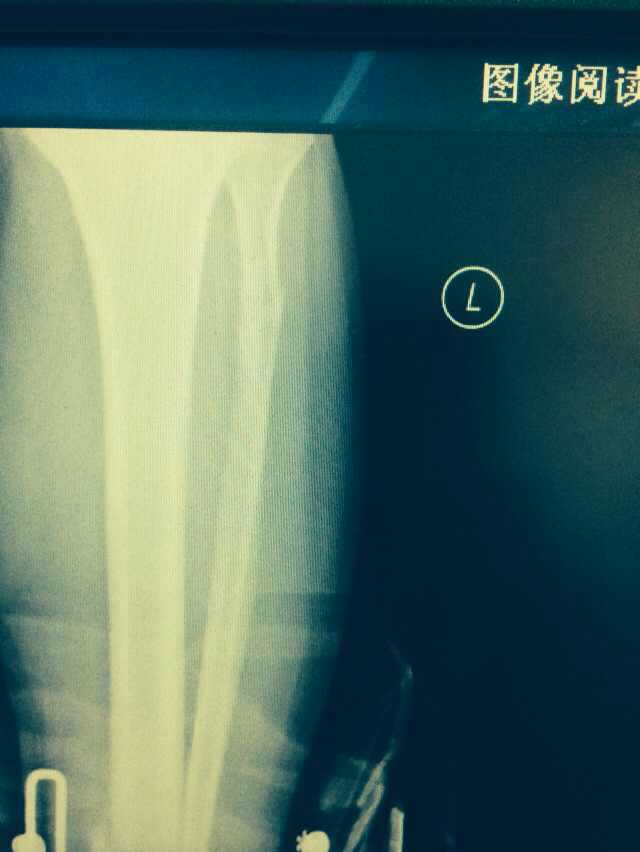

【byb.cn 】(來(lái)源:綜合)2014年12月18日,現(xiàn)年57歲的著名體育評(píng)論員韓喬生,在崇禮云頂滑雪場(chǎng),騎行德國(guó)雪上自行車的時(shí)候,因速度太快,控制不住,韓喬生為避免沖下路基,與一滑行單板的美女相撞,美女因裝備厚,無(wú)大礙,韓喬生則導(dǎo)致左腿脛骨、腓骨兩外骨折,后已經(jīng)被緊急送往北京的醫(yī)院治療。